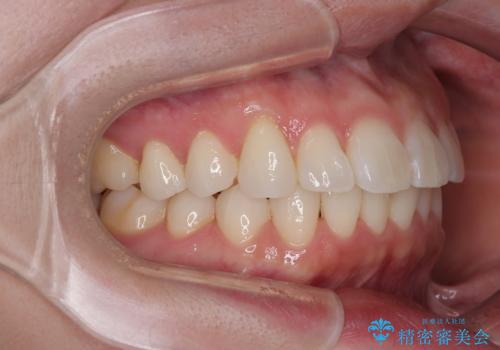

- 上下前歯の叢生を気にして来院された患者様です。

軽度な叢生であり、安価で短期間の治療を規模されていたため、インビザライン・モデレートを用いて矯正治療を行うこととしました。